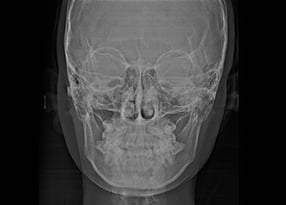

1. 精密検査

このような考えのもと、改めてCTやレントゲン、最新の3D光学スキャナ(iTero)による精密検査を行っております。CT撮影を行わない医院も多いのですが、当院では歯科用CTでの3次元診断も行っています。

2次元のレントゲンではわからない、骨の厚みや顎の幅、歯根の正確な長さ、顎関節の形状を見ながら診断することで、より安全で正確な治療計画を立てられるからです。

4. 詳細シミュレーションの説明(横顔)

さらに当院では、横顔のシミュレーション結果もお見せしています。頭部のレントゲンと横顔の写真を重ねて、横から見たときに口元がどう変化するかをシミュレーションしたものです。

先ほどの歯並びのシミュレーションに加えて、こちらのシミュレーションで、あごや唇がどう変化するか、横顔の見え方がどう変わるか、具体的にご説明いたします。

骨格からととのえる、

精密なバランス分析

矯正治療を行ううえで大切なのは、歯並びだけでなく、骨格や顔全体との調和を考えることです。歯の位置が整っても、顎や輪郭のバランスが取れていなければ、自然な口元にはつながりません。そのため、精密な解析機器を用いて頭部や顎の位置関係を立体的に測定し、骨格レベルでのバランスを数値化しています。治療後の顔の変化をデータとして確認できるため、見た目の印象を左右する口元の位置や輪郭のラインを客観的に把握することができます。

こうした分析をもとに、歯の移動量や方向を細かくシミュレーションし、機能性と美しさの両面からバランスのとれた仕上がりをめざします。単に歯を並べるだけではなく、骨格からととのえることを意識した矯正治療を行っています。